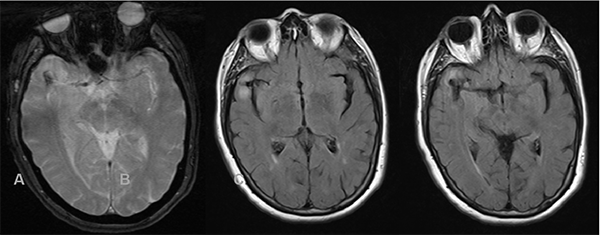

Paciente femenina de 72 años de edad con antecedentes de hipertensión arterial, dislipidemia, sobrepeso y extabaquista, a quien en contexto de estudio por hipoacusia neurosensorial se le realizó RM de cerebro y conductos auditivos internos con contraste endovenoso, en la cual se observó como hallazgo incidental lesión expansiva marcadamente hipointensa en T2 localizada a nivel temporal anterior derecho de aproximadamente 23 x 14 mm de diámetro en relación con el sector distal de la arteria cerebral media homóloga. Tras la inyección de contraste presentó refuerzo heterogéneo, con un componente de aspecto trombosado en el sector basal de la misma, asociado a extenso edema periférico (Figura 3). Se decidió realizar consulta con especialidad de neurocirugía quien sugirió completar la aproximación diagnóstica con AD de vasos intracraneanos en la cual se observó a nivel silviano derecho dilatación aneurismática de contornos lobulados con diámetros de 10.7 x 9.7mm, no presentando un cuello favorable para el acceso endovascular (Figura 4 y 5). En dicho estudio se menciona además pequeño aneurisma de 2mm en arteria comunicante anterior y otro silviano izquierdo de 4mm.

Debido a lo comentado anteriormente se decidió realizar de manera electiva tratamiento quirúrgico convencional con clipado del aneurisma, evolucionando favorablemente y sin complicaciones luego de la misma.